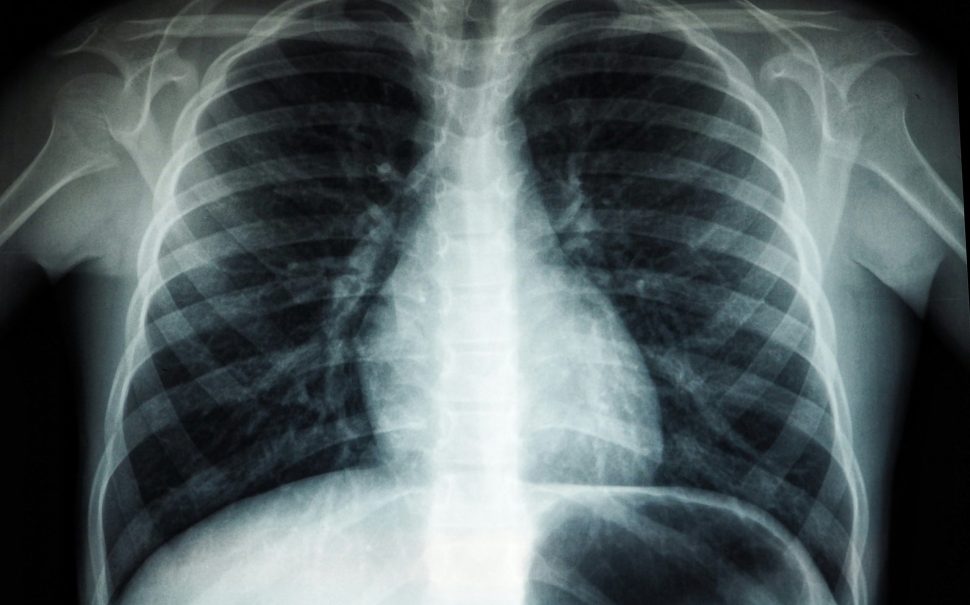

TB primarily affects the lungs and symptoms can come on slowly.

Featured Image: Chest x-ray. Free to use under the Unsplash License.